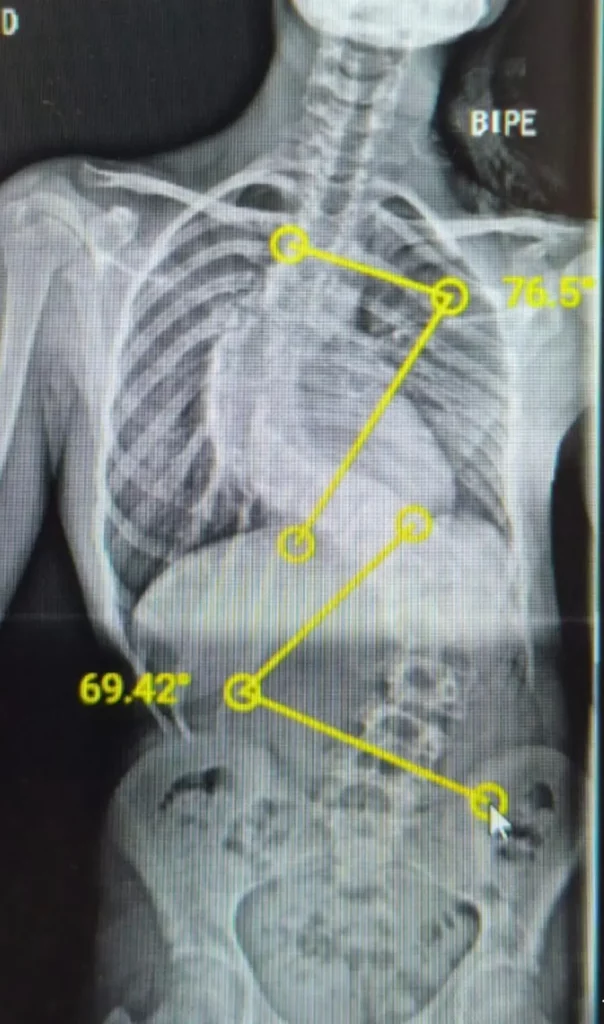

Presentamos el caso de una paciente de 14 años con escoliosis idiopática juvenil, caracterizada por una curva torácica estructurada y una función ventilatoria restrictiva severa en el hemotórax de la concavidad.

La Temporary Internal Distraction (TID) o Distracción Interna Temporal, también conocida como técnica de Skaggs, es una estrategia quirúrgica en dos tiempos utilizada en casos de escoliosis de alto grado (>90º), especialmente en pacientes pediátricos. Permite una corrección progresiva de la curvatura espinal sin comprometer la seguridad neurológica ni recurrir a tracción externa.

– Curvas iniciales promedio: 104º.

– Corrección post-distracción: 53% (de 104º a 49º).

– Corrección final tras fusión: 80% (de 104º a 20º).